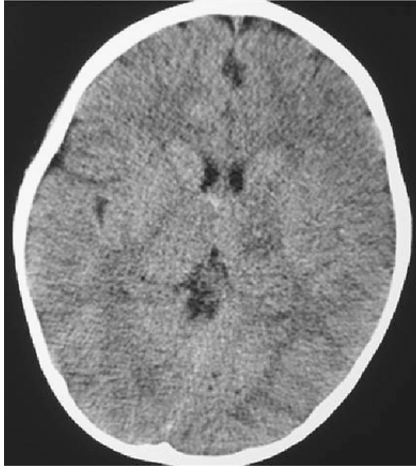

42

subdural hematoma R fronto temporal

subacute subdural hematomas are _______ on CT; chronic are ______ on CT.

* isodense (difficult to ID) * hypodense (dark)